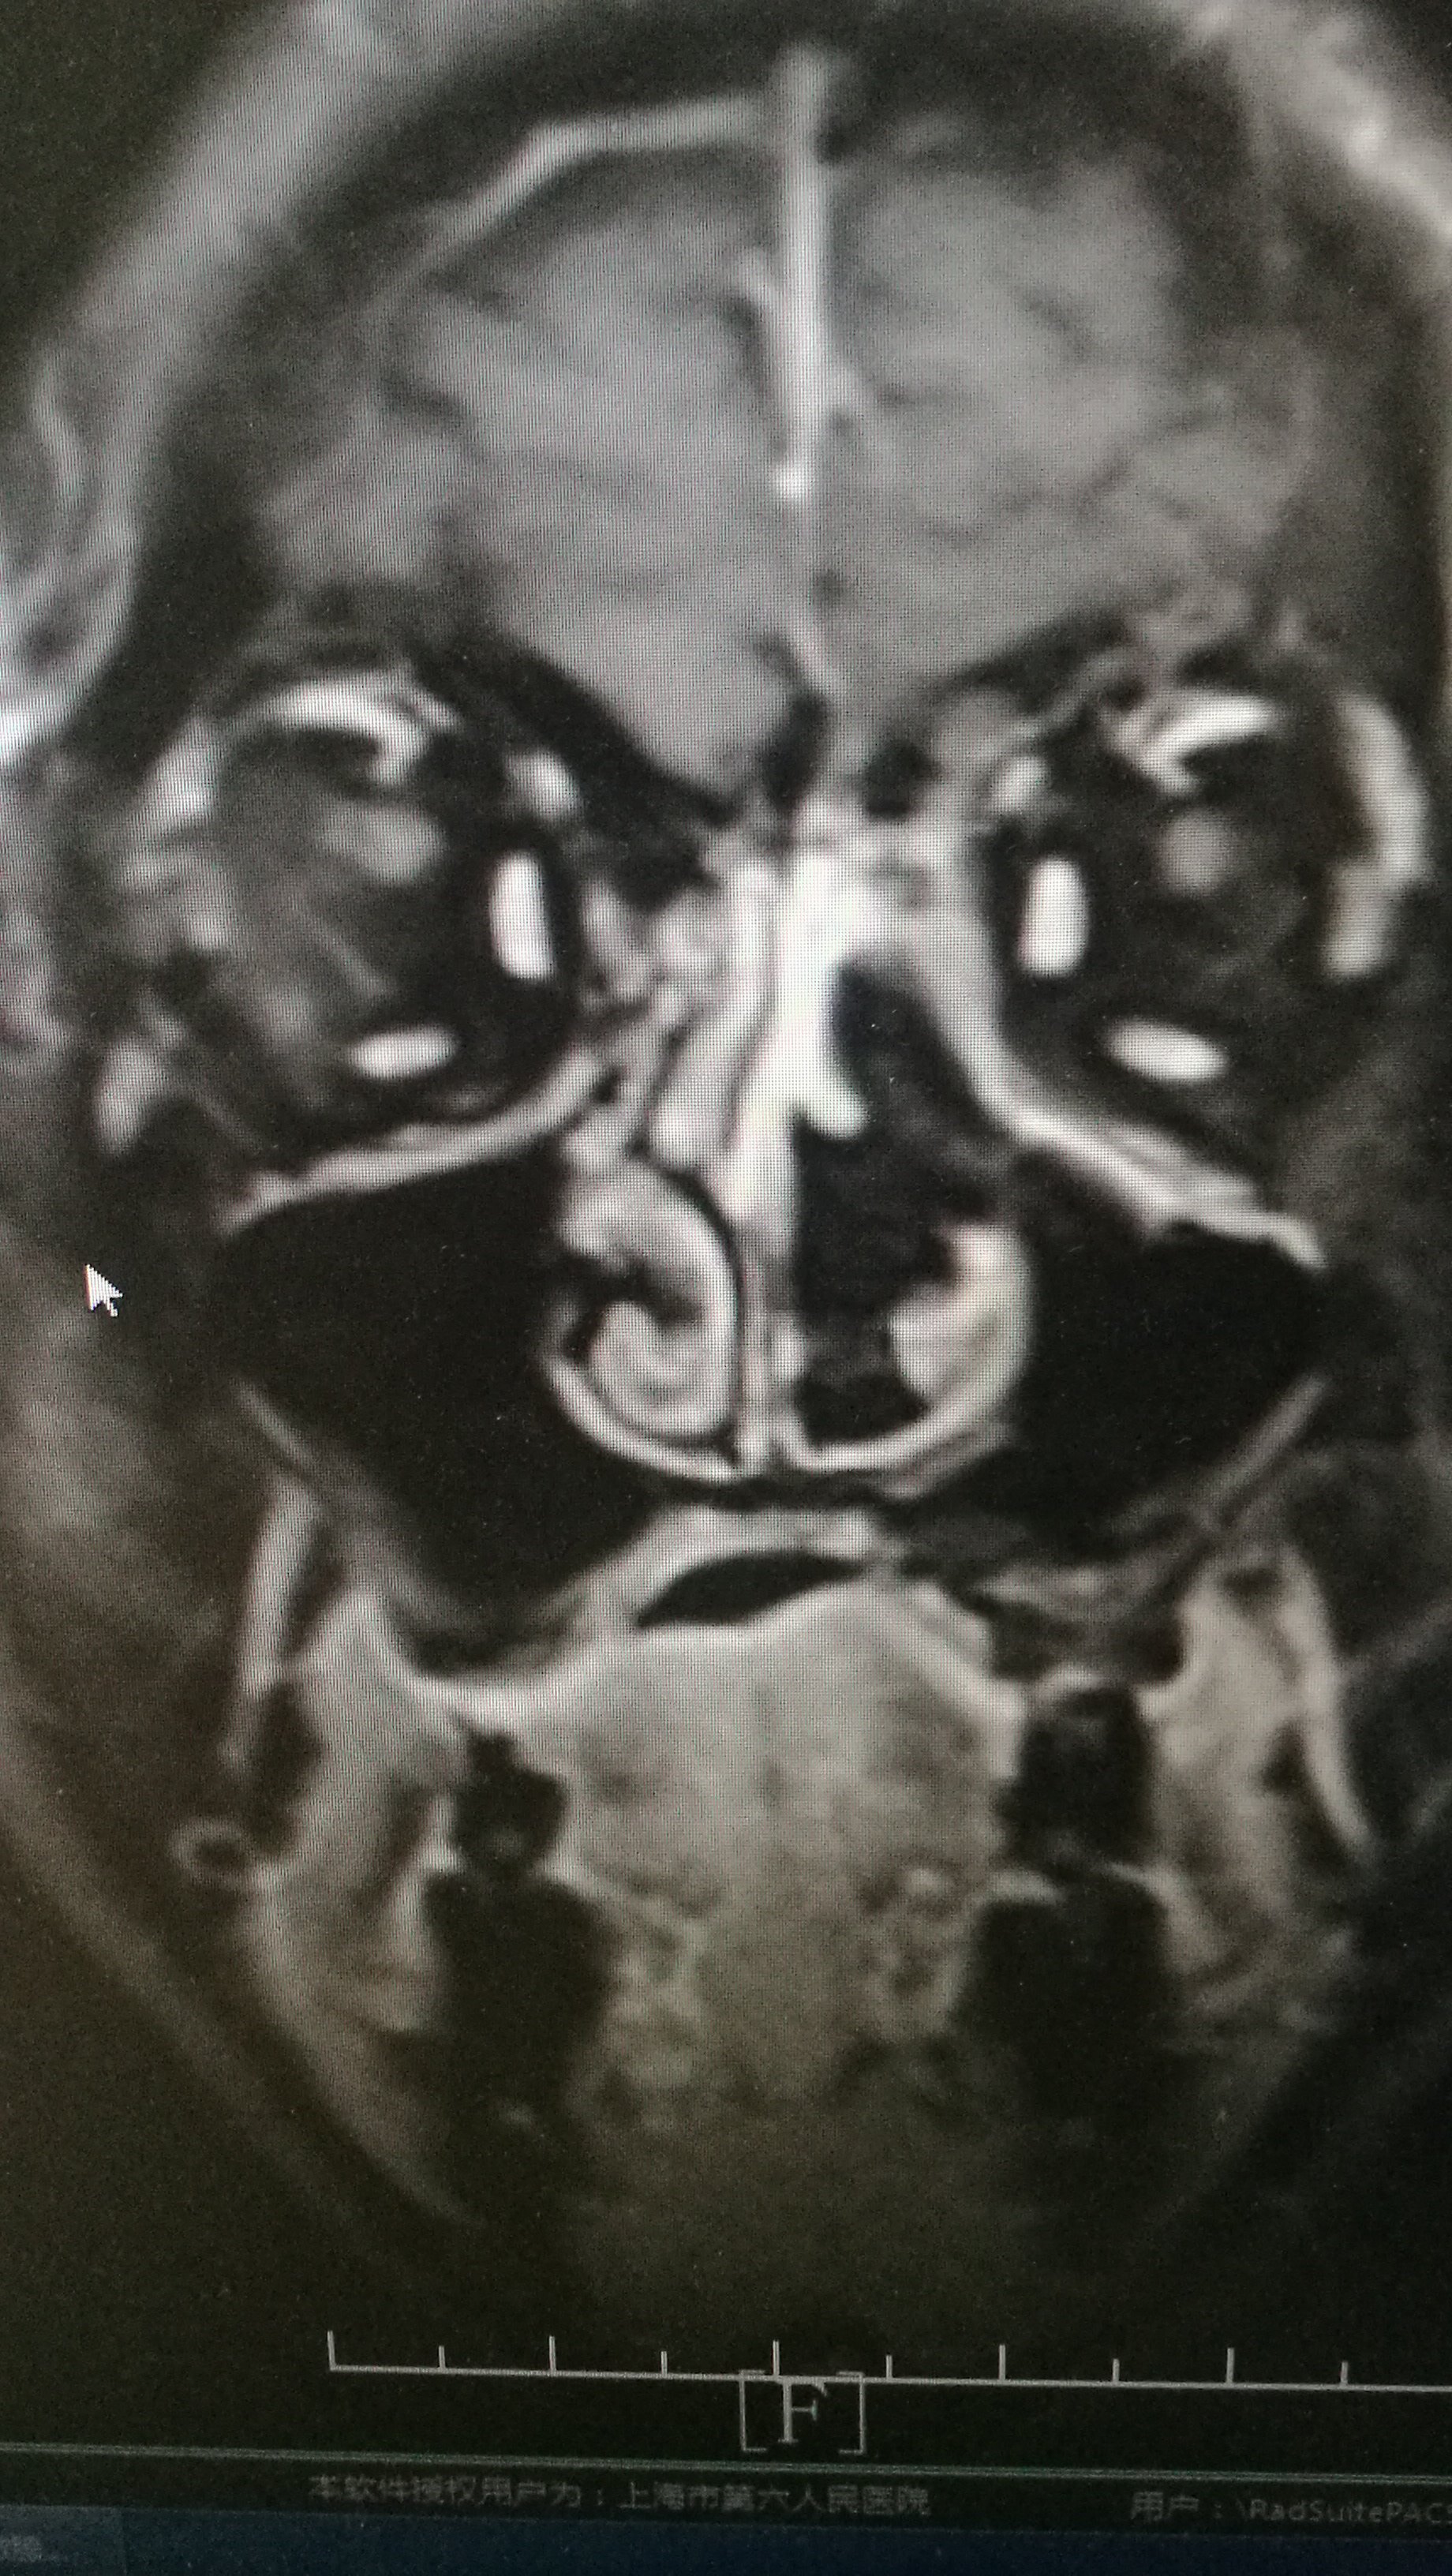

医联#复发性鼻腔鼻窦内翻性乳头状瘤一例

鹤壁市中医院耳鼻喉科 右侧上颌窦占位(内翻性乳头状瘤?

鼻涕带血鼻塞要小心鼻腔肿瘤内翻乳头状瘤图

一,鼻腔鼻窦乳头状瘤 耳鼻咽喉科医院 主要发生在鼻腔鼻窦 多见于 40